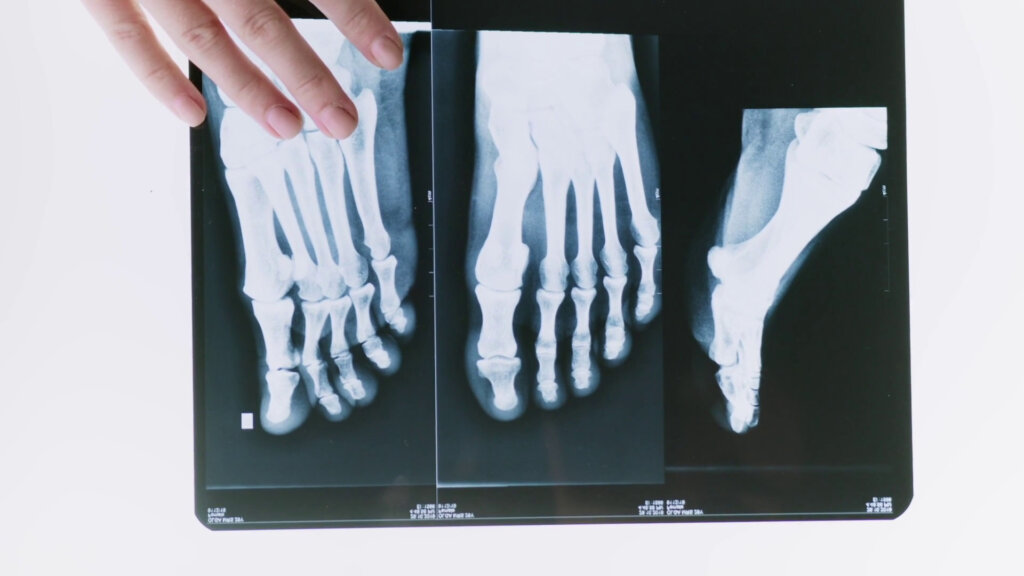

MILANO (ITALPRESS) – La frattura è un’interruzione nella continuità di un osso in due o più parti. Ci sono varie modalità di classificazione, la prima è in base alle cause che la determinano: le fratture patologiche si verificano quando l’osso è malato, quelle traumatiche quando la parte è colpita da un evento esterno, a bassa o alta energia. Altri criteri definiscono le fratture come chiuse o esposte, complicate o semplici, composte o scomposte, stabili o instabili. Sono alcuni dei temi trattati da Andrea Mambretti, specialista in ortopedia e traumatologia e dirigente medico della traumatologia sportiva del Centro specialistico ortopedico-traumatologico Gaetano Pini di Milano, intervistato da Marco Klinger per Medicina Top, format tv dell’agenzia di stampa Italpress.